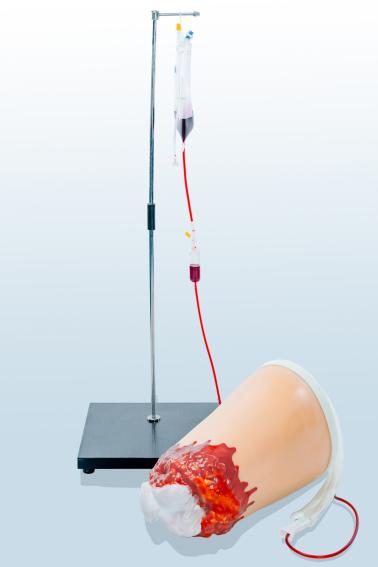

上肢外伤断肢止血模型

上肢外伤断肢止血模型

下肢外伤断肢止血模型

下肢外伤断肢止血模型